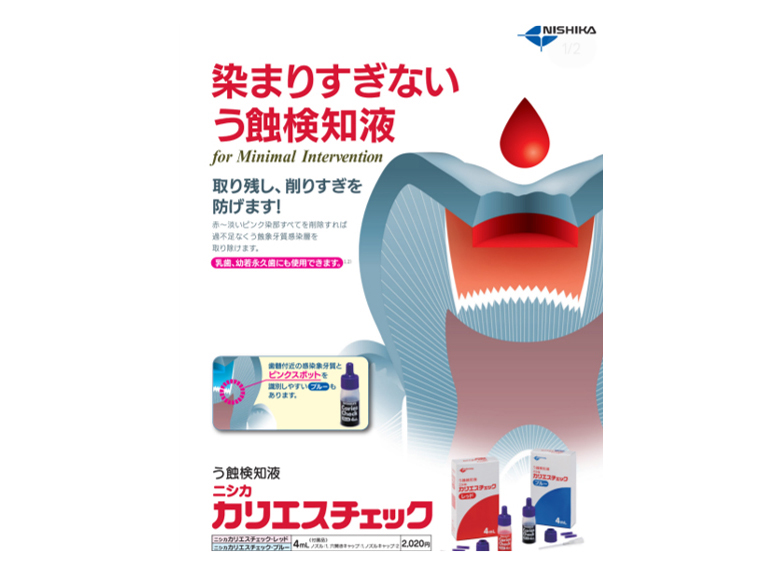

POINTむし歯箇所を可視化する検知液

むし歯に反応する専用の薬液です。

カリエスチェックを塗布し、水洗後、色が残っている部分がむし歯です。むし歯の取り残しを無くすことと、不必要に歯を削りすぎてしまうことがないようにするための確認のために使用します。